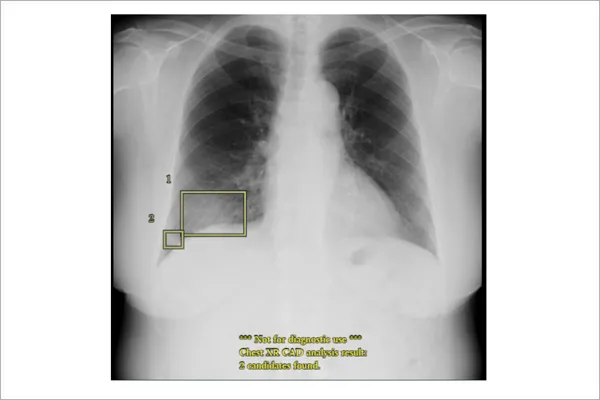

胸部レントゲンAI画像診断支援システム(エルピクセル社製 EIRL Chest)

- 胸部X線画像における異常所見の検出を支援するため、エルピクセル社のAI画像診断支援システム「EIRL(エイル)Chest」を導入

- AIのディープラーニング技術を活用し、肺がん、肺炎、気胸などの異常陰影を自動で検出・強調表示します。医師の診断をサポートすることで、見逃しのリスクを軽減し、より正確で迅速な診断につなげることが可能

- 医師単独の読影と比べ、全体として12.5%の感度上昇するとされ、医師の経験と組み合わせることにより、より安心な検査体制を構築することが可能